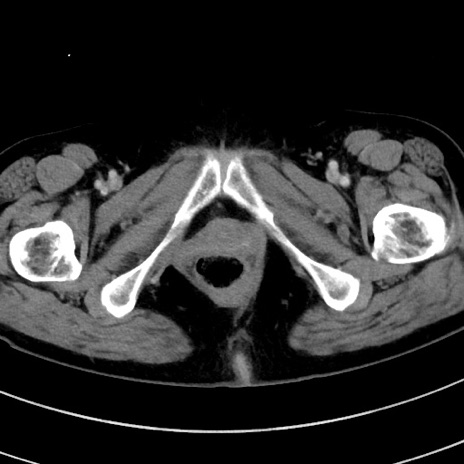

症例9(横断像)

【症例】 60歳代女性

【主訴】むかつき、みぞおちの痛み

【現病歴】3日前よりむかつきがあり、食事がとれない。

【既往歴】糖尿病

【身体所見】発熱なし、心窩部圧痛軽度あるも、腹膜刺激症状なし。

【データ】WBC 7400、CRP 1.92